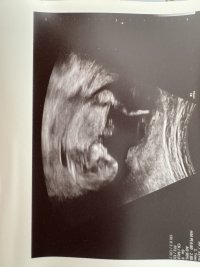

Syns dette ser veldig ut som en gutt, pga det «laget» oppå + at den går oppover. Men har du noen flere bilder?13+2 noen som har en tanke her? Synst selv nubben her er mye flatere enn med gutten jeg har

Har disse, men tror ikke nub viser herSyns dette ser veldig ut som en gutt, pga det «laget» oppå + at den går oppover. Men har du noen flere bilder?![]()

Siste bilde så kan se se ut som en guttHar disse, men tror ikke nub viser her